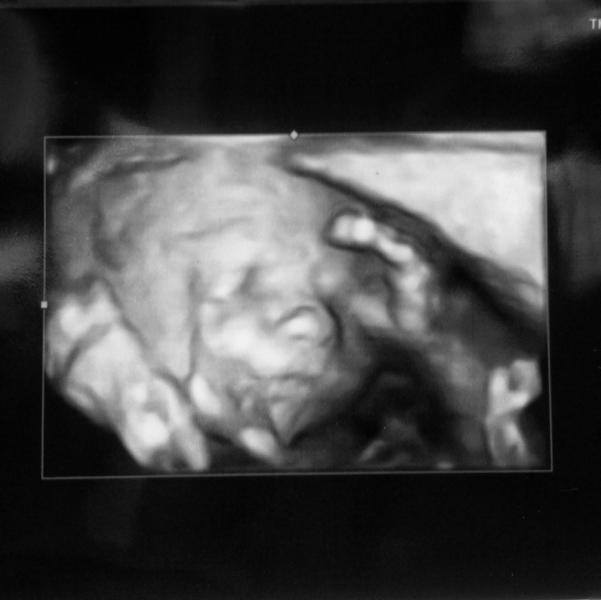

Вчера была на втором скрине, и помимо всех измерений ножек, ручек и усиков, конечно сделали фото лица! Как я понимаю, это при хорошем оборудовании даже обязательно - посмотреть в 3D, в целях исключения всяческих уродств. Так вот, свекровь очень рада была посмотреть на фотки, но на мои слова, что малыш ручками и пуповиной закрывался и не давал фото сделать, она сказала, что мол не надо смотреть на то, что пока скрыто. У моего п...